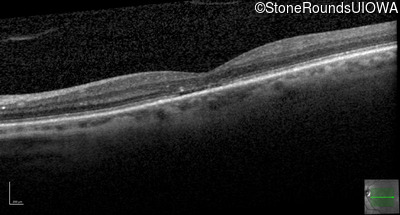

The clinical features supporting the diagnosis of blue cone monochromacy in this patient include: stable reduced acuity, photophobia and very poor color vision since early childhood, a normal fundus appearance, normally sighted parents and three similarly affected male relatives on the maternal side of his family.

Age at visit: 58 years

Age at visit: 59 years